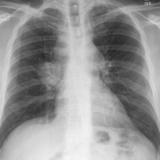

BAC

Album: BAC

Date: 09/10/2006

Size: 9 items

Views: 41508